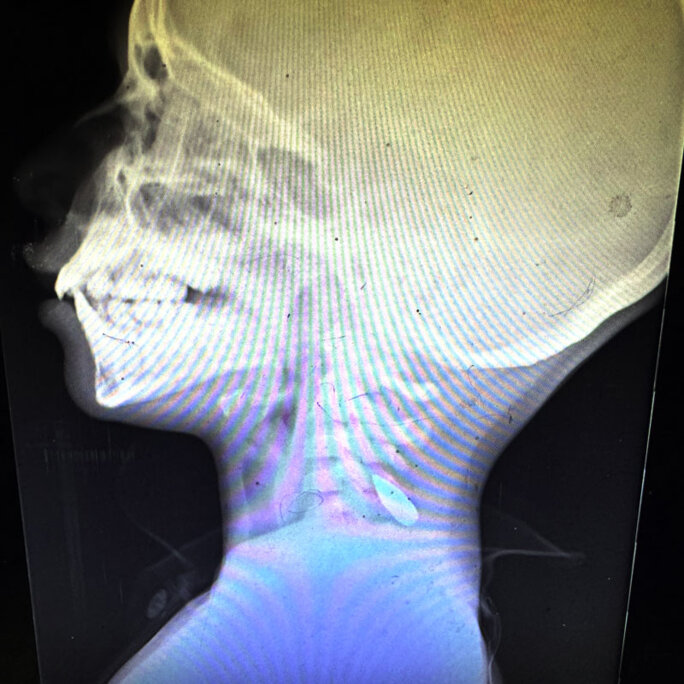

Agrandir l'image : Illustration 1

Agrandir l'image : Illustration 2

Agrandir l'image : Illustration 3

Ces radiographies montrant des enfants de Gaza avec des balles dans le cou ou la tête ont été partagées par le Dr Mimi Syed, qui a travaillé à Khan Younis du 8 août au 5 septembre. Elle a expliqué : « J'ai pris en charge de nombreux jeunes patients, pour la plupart âgés de moins de 12 ans, atteints d'une balle dans la tête ou dans la poitrine, sur le côté gauche. En général, il s'agissait d'une seule balle. Les enfants arrivaient soit déjà morts, soit dans un état critique, et mouraient peu après leur arrivée. »